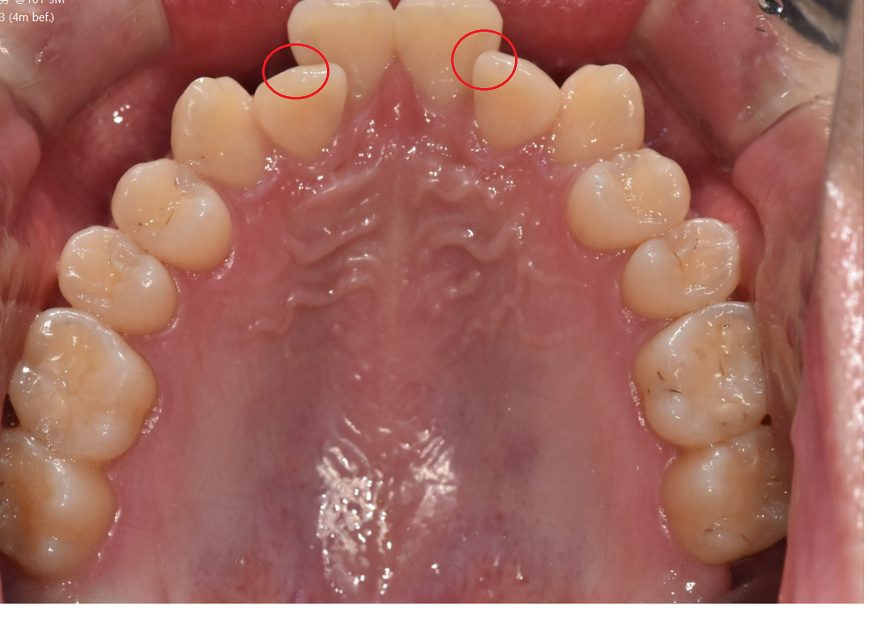

사진처럼 다른 치아에 비하여 안쪽으로 들어가 있기도 하고

튀어 나와있는 경우도 있지만

치아 배열이 울퉁불퉁한 것이라 보시면 됩니다.

250616 양치가 어렵겠죠?

들어가 있는 치아와 나와있는 치아

불규칙한 치아 배열로 칫솔질이 어렵고

양치가 잘 안되는 사각지대가 생길 수 있겠죠??